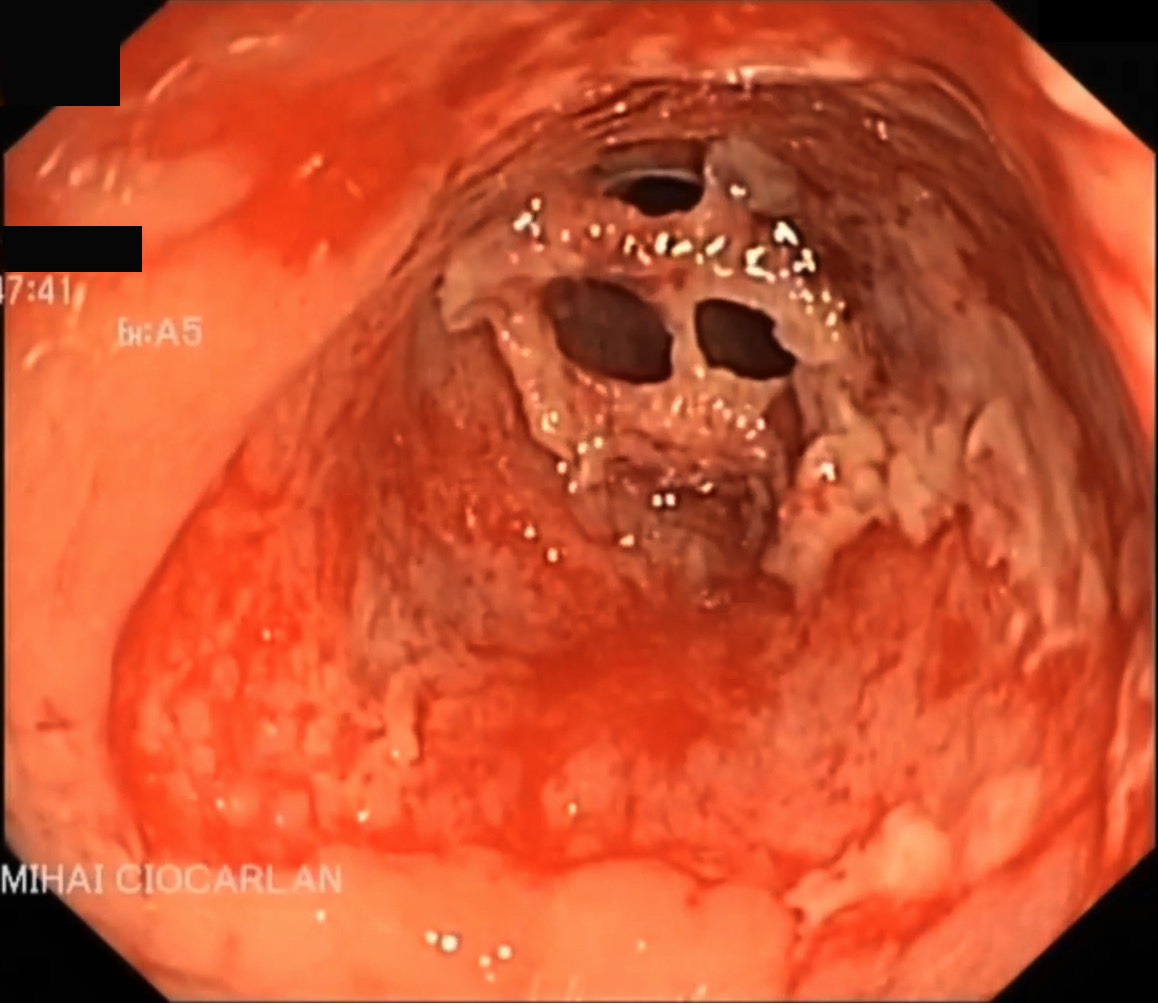

More than half of CD patients with perianal lesions have multiple lesions [56]. Fig. 2 shows typical lesions at colonoscopy in a patient with CD.

Fig. 2.Colonoscopy aspect of CD: a narrow colonic stricture with ulcerated mucosa. CD, Crohn’s disease.